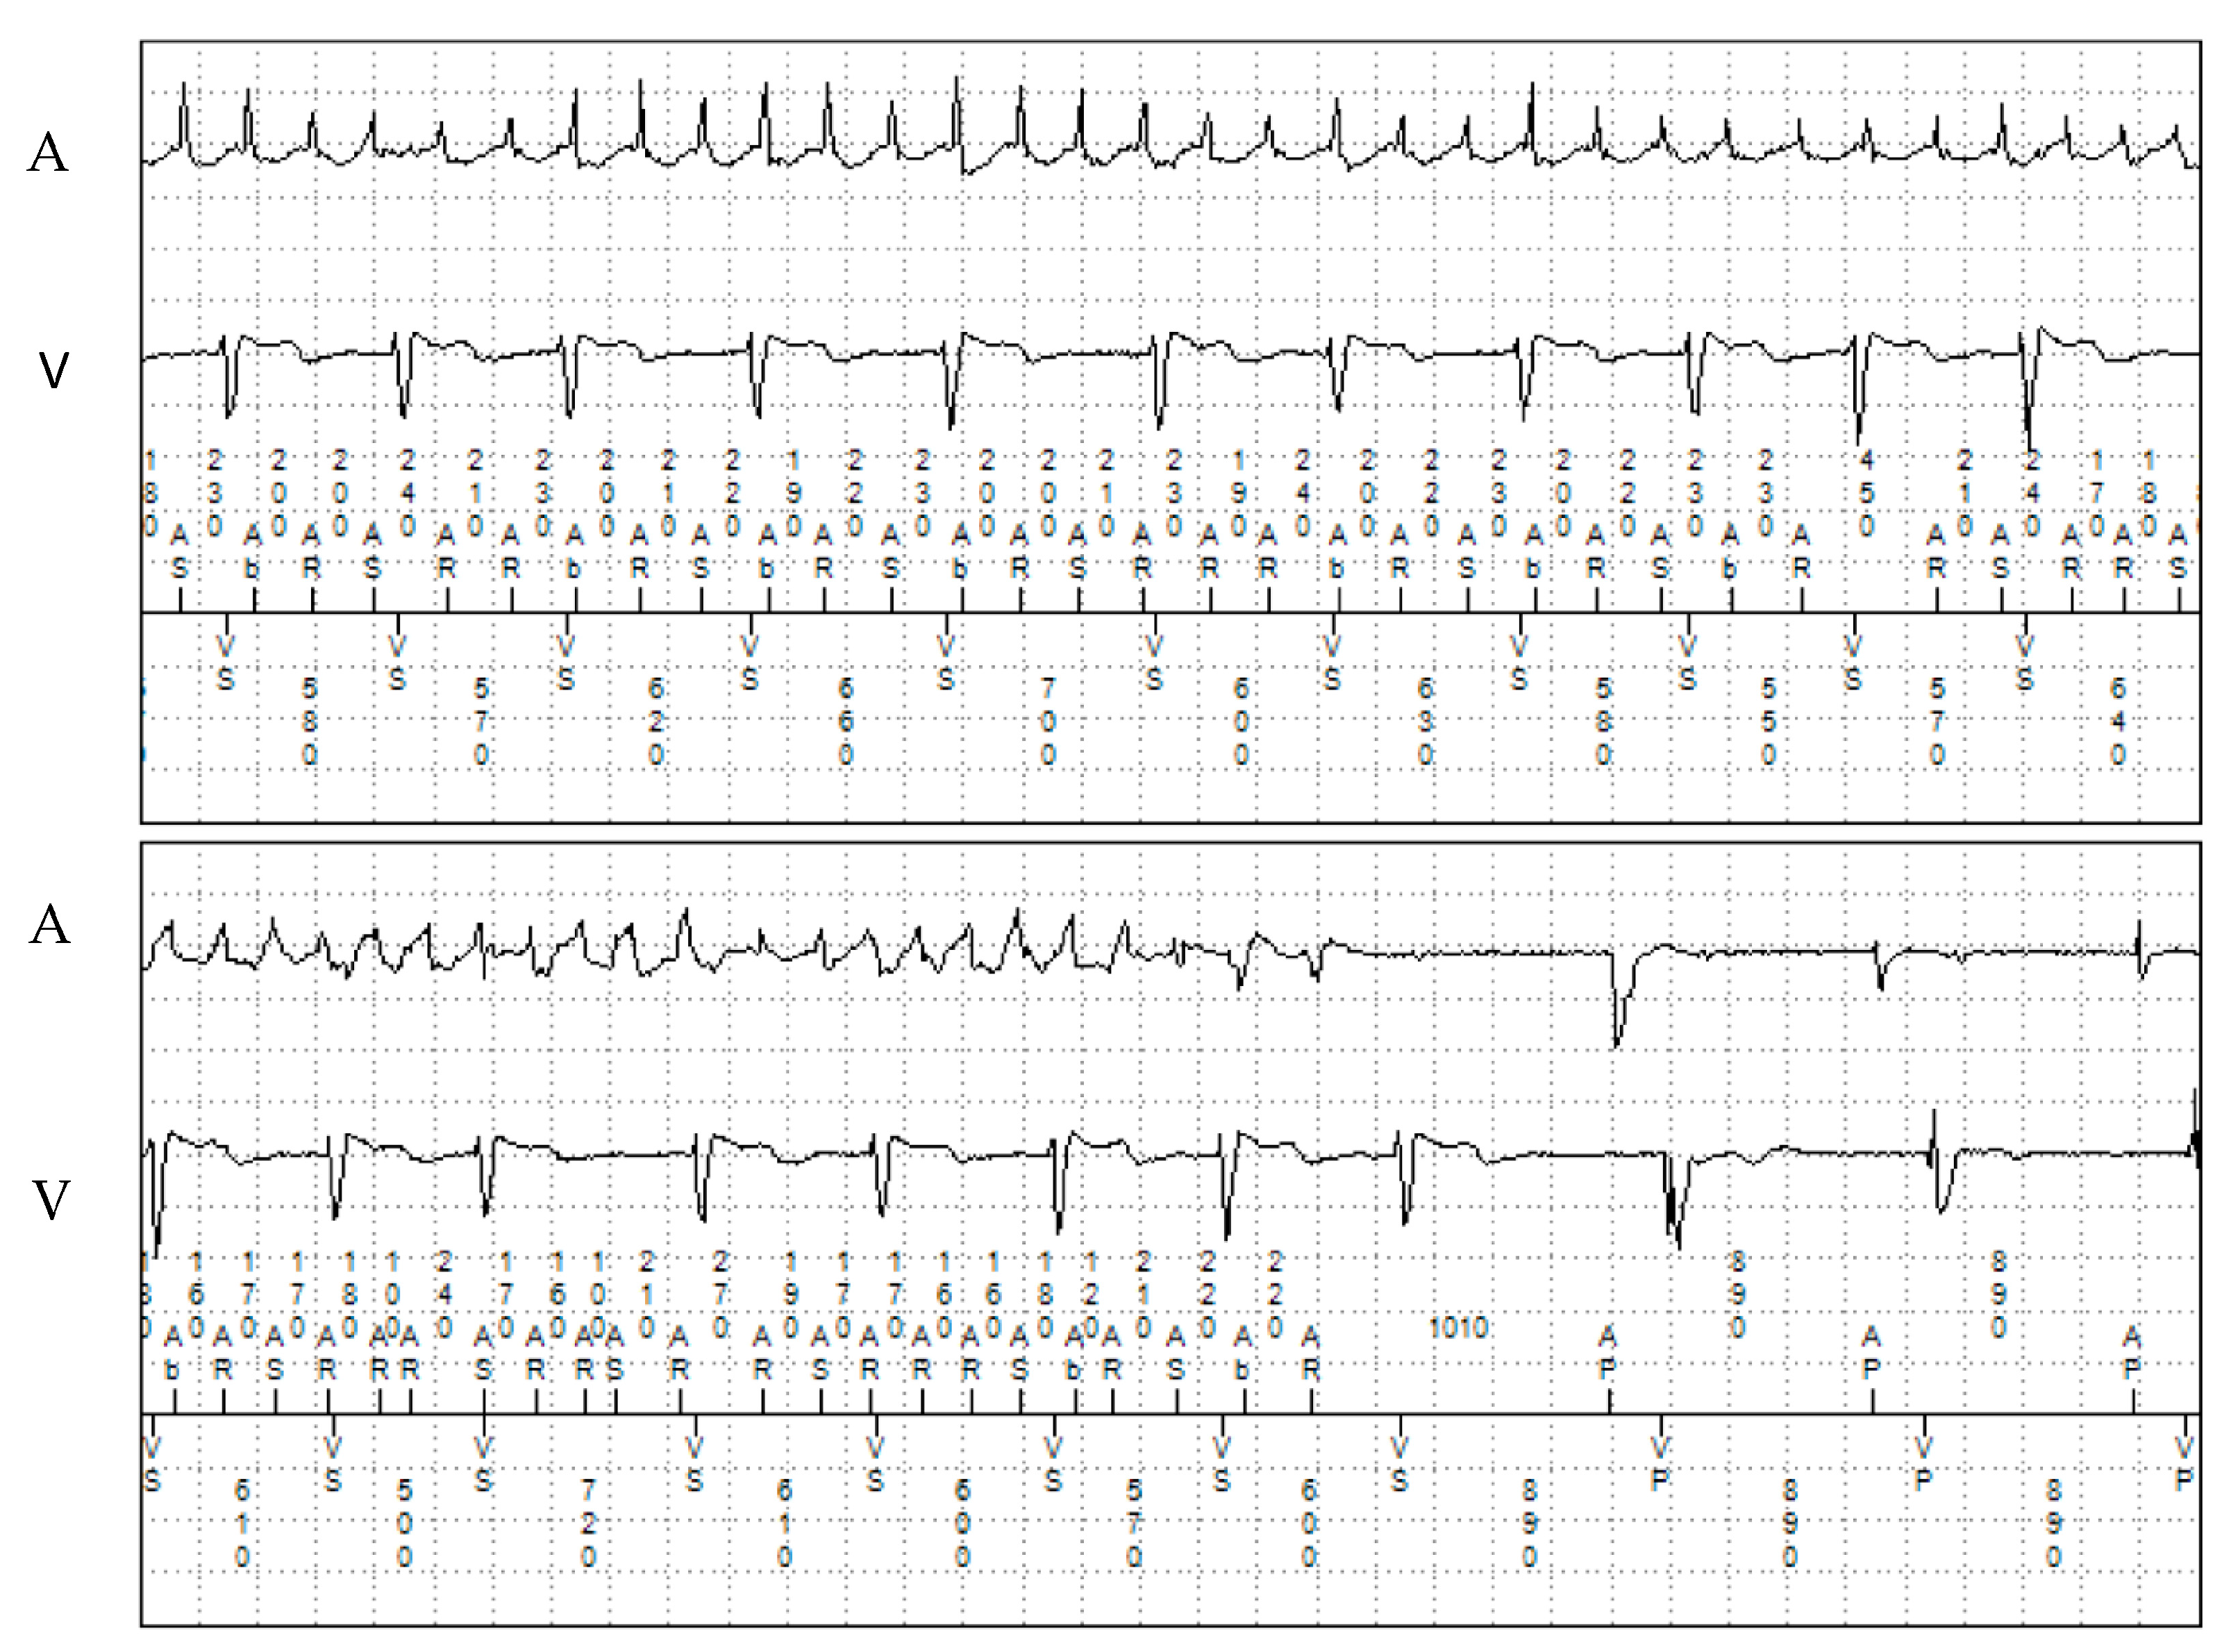

The proband, a 31-year-old man, suffered a syncope during physical activity and was diagnosed with CPVT at the age of 12. TTE showed a structurally normal heart. He underwent implantation of a dual-chamber epicardial ICD. The patient underwent refixation of the pleural defibrillation electrode one year after implantation due to system dysfunction. At the age of 18, the patient experienced ventricular fibrillation (VF), which was adequately detected and successfully terminated by the implanted device. After this episode, propranolol dosage was increased, with no recurrent ventricular tachyarrhythmias occurring since then. Multiple asymptomatic episodes of paroxysmal AF were detected with remote monitoring (Figure 3 and Figure 4). No oral anticoagulation was prescribed, given his CHA2DS2-VASc score of 0.

Figure 3. Episode of atrial fibrillation on remote monitoring with the dual-chamber ICD in patient 2. A: atrial electrogram; V: ventricular electrogram.

Figure 4. Episode of atrial tachycardia and ventricular ectopy in patient 2. A: atrial electrogram; V: ventricular electrogram.